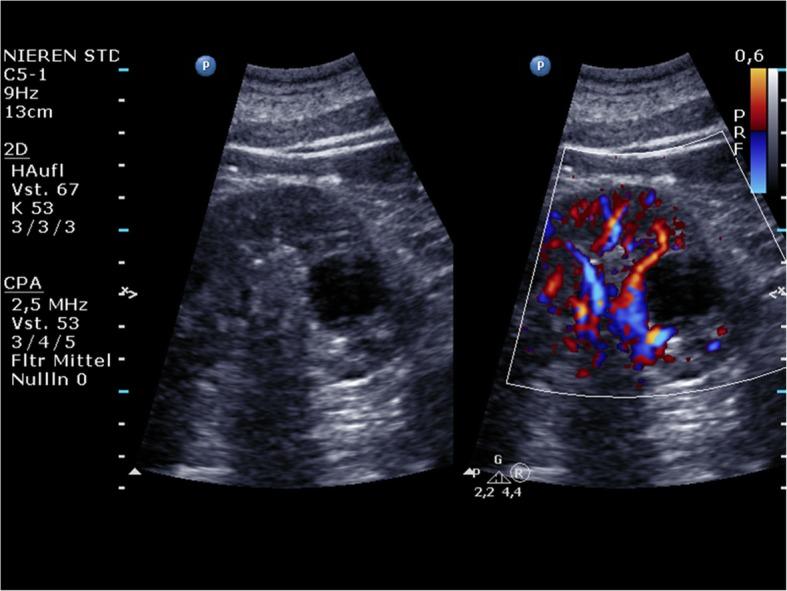

The use of portable ultrasound (US) devices has increased in recent years and the market has been flourishing. Portable US devices can be subdivided into three groups: laptop-associated devices, hand-carried US, and handheld US devices. Almost all companies we investigated offer at least one portable US device. Portable US can also be associated with the use of different US techniques such as colour Doppler US and pulse wave (PW)-Doppler. Laptop systems will also be available with contrast-enhanced US and high-end cardiac functionality.Portable US devices are effective in the hands of experienced examiners. Imaging quality is predictably inferior to so-called high-end devices.The present paper is focused on portable US devices and clinical applications describing their possible use in different organs and clinical settings, keeping in mind that patient safety must never be compromised. Hence, portable devices must undergo the same decontamination assessment and protocols as the standard equipment, especially smartphones and tablets.

近年来,便携式超声(US)设备的使用有所增加,市场蓬勃发展。便携式超声设备可细分为三类:与笔记本电脑相关的设备、手提式超声设备和手持式超声设备。我们调查的几乎所有公司都至少提供一种便携式超声设备。便携式超声还可与不同的超声技术结合使用,如彩色多普勒超声和脉冲波(PW)多普勒。笔记本电脑系统还将具备超声造影增强功能和高端心脏功能。便携式超声设备在经验丰富的检查人员手中是有效的。成像质量预计低于所谓的高端设备。本文重点关注便携式超声设备及其临床应用,描述它们在不同器官和临床环境中的可能用途,同时牢记绝不能损害患者安全。因此,便携式设备必须与标准设备,尤其是智能手机和平板电脑,接受相同的去污评估和规程。